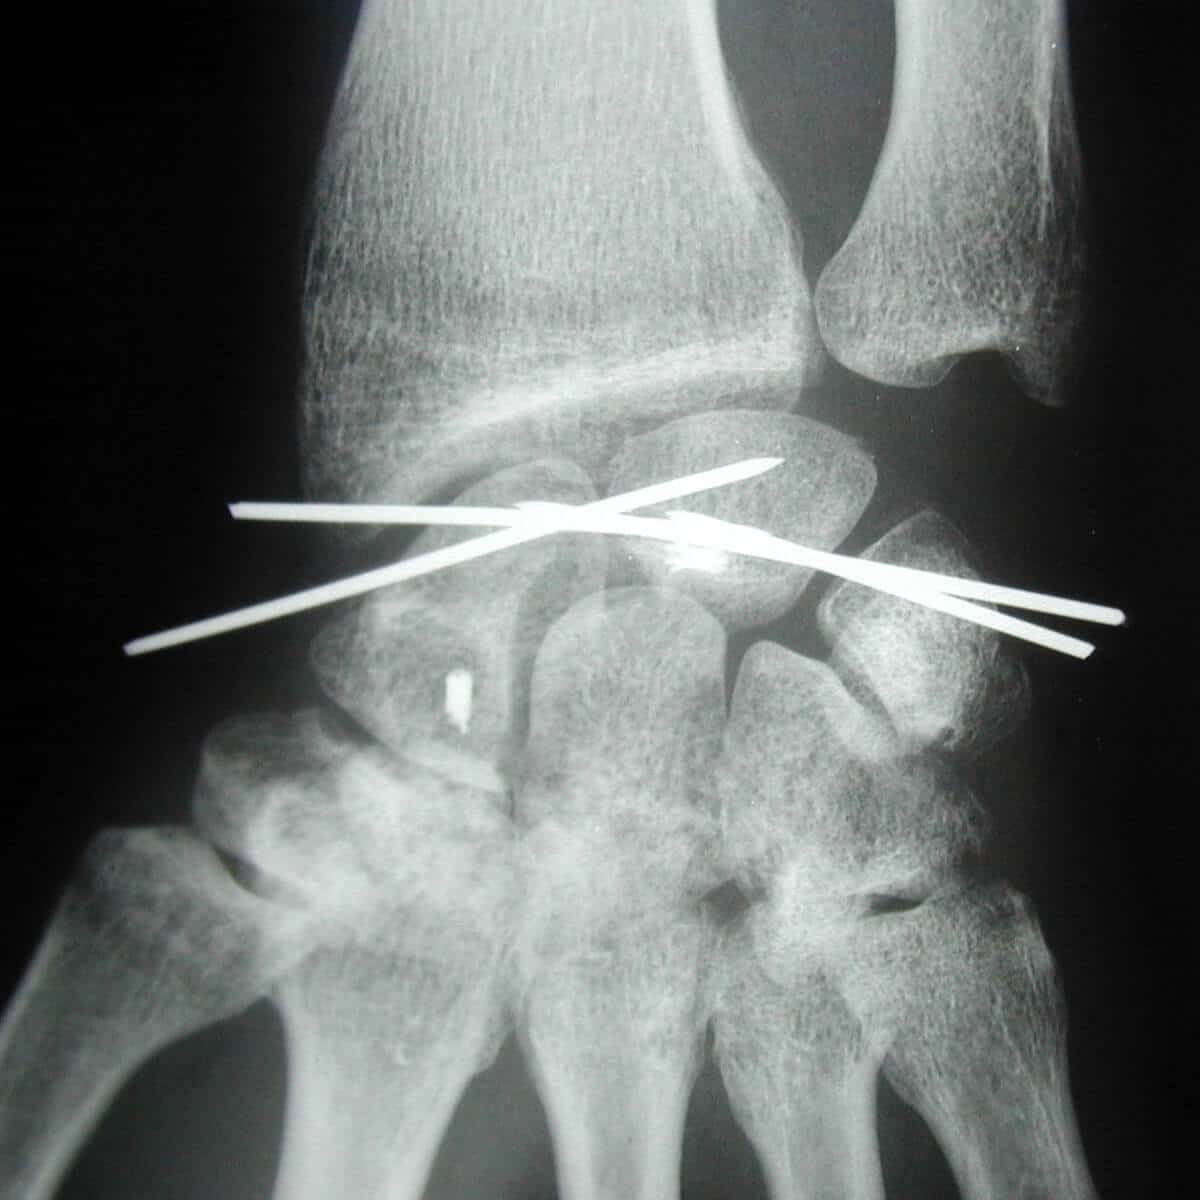

operation chirurgicale entorse au poignet grave

Entorse grave opérée par embrochage multiple scapho lunarien